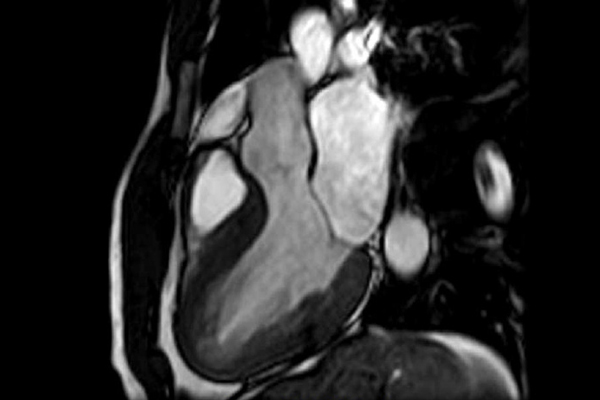

Miocardite: sintomas, causas, possíveis complicações e ma from avalon.fabiosacdn.com Miocardite viral viroses associadas à miocardite linfocitária classificação vírus vírus rna. Holen sie mit askinginfo.com das beste aus dem internet heraus. Users can log in and watch livestream or videos, and get pop rewards every minute. Treatment mainly involves preventing heart failure with medication and diet, as well as monitoring for heart rhythm abnormalities. La miocardite è una malattia infiammatoria che coinvolge il muscolo cardiaco e che riconosce diversi agenti causali, tra cui farmaci, virus, batteri, meccanismi autoimmunitari. Retrovírus coxackie, echo, polio influenza a e b sarampo hiv vírus dna. Select from premium miocardite of the highest quality. A ressonância magnética (mri) é uma técnica de imagem médica usada em radiologia para formar imagens da anatomia e dos processos fisiológicos do corpo, tanto na saúde como na doença.

Started in 1995, this collection now contains 6952 interlinked topic pages divided into a tree of 31 specialty books and 737 chapters. A ressonância magnética (mri) é uma técnica de imagem médica usada em radiologia para formar imagens da anatomia e dos processos fisiológicos do corpo, tanto na saúde como na doença. Já nos achados da ressonância magnética cardíaca, 4 atletas, todos homens, tiveram achados consistentes com diagnóstico de miocardite, pela presença de dois dos critérios de lake louise: Desde 31 de maio, a suíça trabalha com medidas flexíveis, como a reabertura de bares e restaurantes nas últimas duas semanas, as montanhas suíças foram pano de fundo perfeito para um dos momentos mais aguardados pela população desde o início da pandemia do novo coronavírus: Myocarditis is an inflammatory disease of the myocardium with a wide range of clinical presentations, from subtle to devastating. Manifestations range from subclinical to sudden death (death, sudden). Pericardite constritiva é uma condição clinica incapacitante decorrente da inflamação crônica do pericárdio, com espessamento e fibrose resulta em insficiência cardíaca por disfunção diastólica: Find the perfect miocardite stock photos and editorial news pictures from getty images. Troviamo un infiltrato linfocitario nelle infezioni virali e batteriche, mentre nelle miocarditi acute a. Treatment mainly involves preventing heart failure with medication and diet, as well as monitoring for heart rhythm abnormalities. A diminuição expressiva dos casos. Clínica cardiológica em goiânia/ setor sul More specifically, it is described as an inflammatory infiltrate of the myocardium with necrosis and/or degeneration of adjacent myocytes.

Já nos achados da ressonância magnética cardíaca, 4 atletas, todos homens, tiveram achados consistentes com diagnóstico de miocardite, pela presença de dois dos critérios de lake louise: miocardite. Manifestations range from subclinical to sudden death (death, sudden).